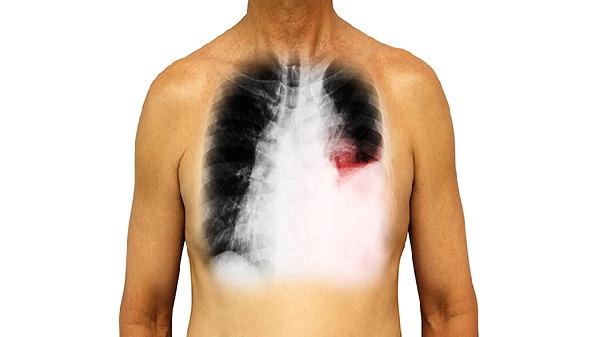

左肺上叶尖后段病变通常指影像学检查发现的该区域异常表现,可能由肺炎、肺结核、肺结节或肿瘤等疾病引起。

肺炎是左肺上叶尖后段病变的常见原因之一,多由细菌或病毒感染导致,患者可能出现咳嗽、发热、胸痛等症状。肺结核也可累及该区域,典型表现为低热、盗汗、消瘦等结核中毒症状,影像学可见空洞或钙化灶。肺结节多为良性病变,但需警惕恶性可能,定期随访观察结节变化很重要。肿瘤性病变包括原发性肺癌或转移瘤,早期可能无明显症状,随病情进展可出现咯血、呼吸困难等表现。部分患者可能因支气管扩张或肺脓肿等疾病引起局部病变,伴随咳脓痰、反复感染等症状。